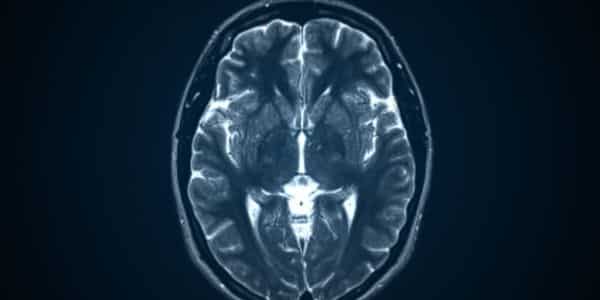

Resonancia de cerebro/cabeza

La resonancia magnética (RM) de cerebro es un examen que genera imágenes precisas del encéfalo, los vasos sanguíneos, los nervios craneales y otras estructuras internas del cráneo.

Este estudio es clave para identificar y analizar diversas afecciones del sistema nervioso central, como tumores, accidentes cerebrovasculares, malformaciones congénitas, esclerosis múltiple, infecciones, aneurismas o las causas de dolores de cabeza crónicos, facilitando un diagnóstico detallado y un seguimiento efectivo del tratamiento.

Precio desde: 170€